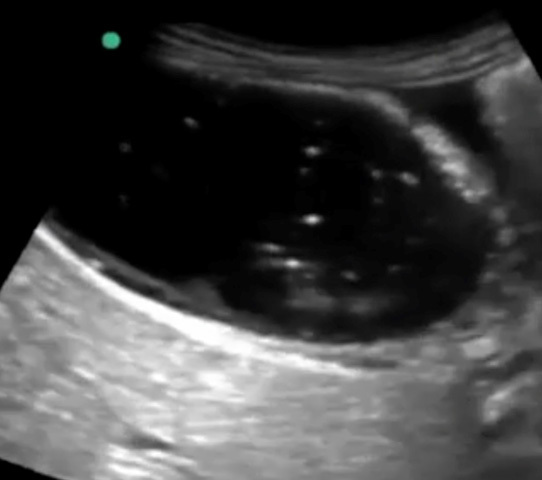

Gallbladder Sonographic Murphy’s Sign Common Bile Duct (CBD) – Transverse Image